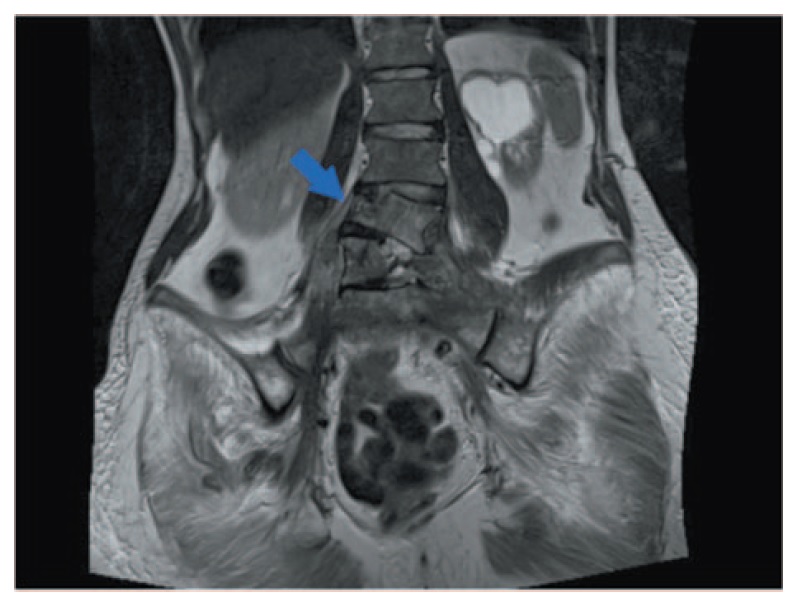

В 2017 г. появились боли в левой нижней конечности, по результатам МРТ выявлены перелом поясничного позвонка, множественные метастазы в парааортальных лимфатических узлах, метастатический инфильтрат с вовлечением левого мочеточника, большой поясничной мышцы, широчайшей мышцы спины слева, позвонки L5, S1 (рис. 1). Проведено 6 циклов ХТ по стандартной схеме: паклитаксел + карбоплатин с добавлением золедроновой кислоты с эффектом стабилизации опухолевого процесса в течение 6 мес.

Рис. 1. Деструкция тел позвонков L4, L5, S1. / Fig. 1. Destruction of the L4, L5, S1 vertebral bodies.